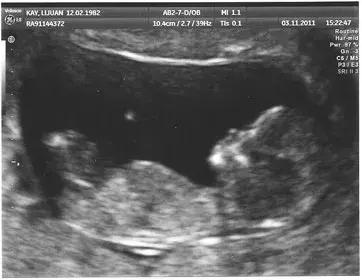

06 心脏、胎儿超声检查

心脏、胎儿超声是超声检查的优势项目,心脏和胎儿异常往往都是通过超声检查出来的,先天性和后天性心脏病以及心脏功能评估,超声检查是最具优势的方法,也是超声检查的常见内容。

胎儿超声检查更是超声检查的独有优势,20年前大家还不太能接受超声胎儿检查,担心对孩子有影响,不过现在大家都有了超声孕检的观念,在孕期中孕大排畸检查(三级筛查)已经广为大家所接受,对国家优生优孕有重大的促进作用。不过早中孕系统筛查也非常重要,而目前仍未被大家所重视。